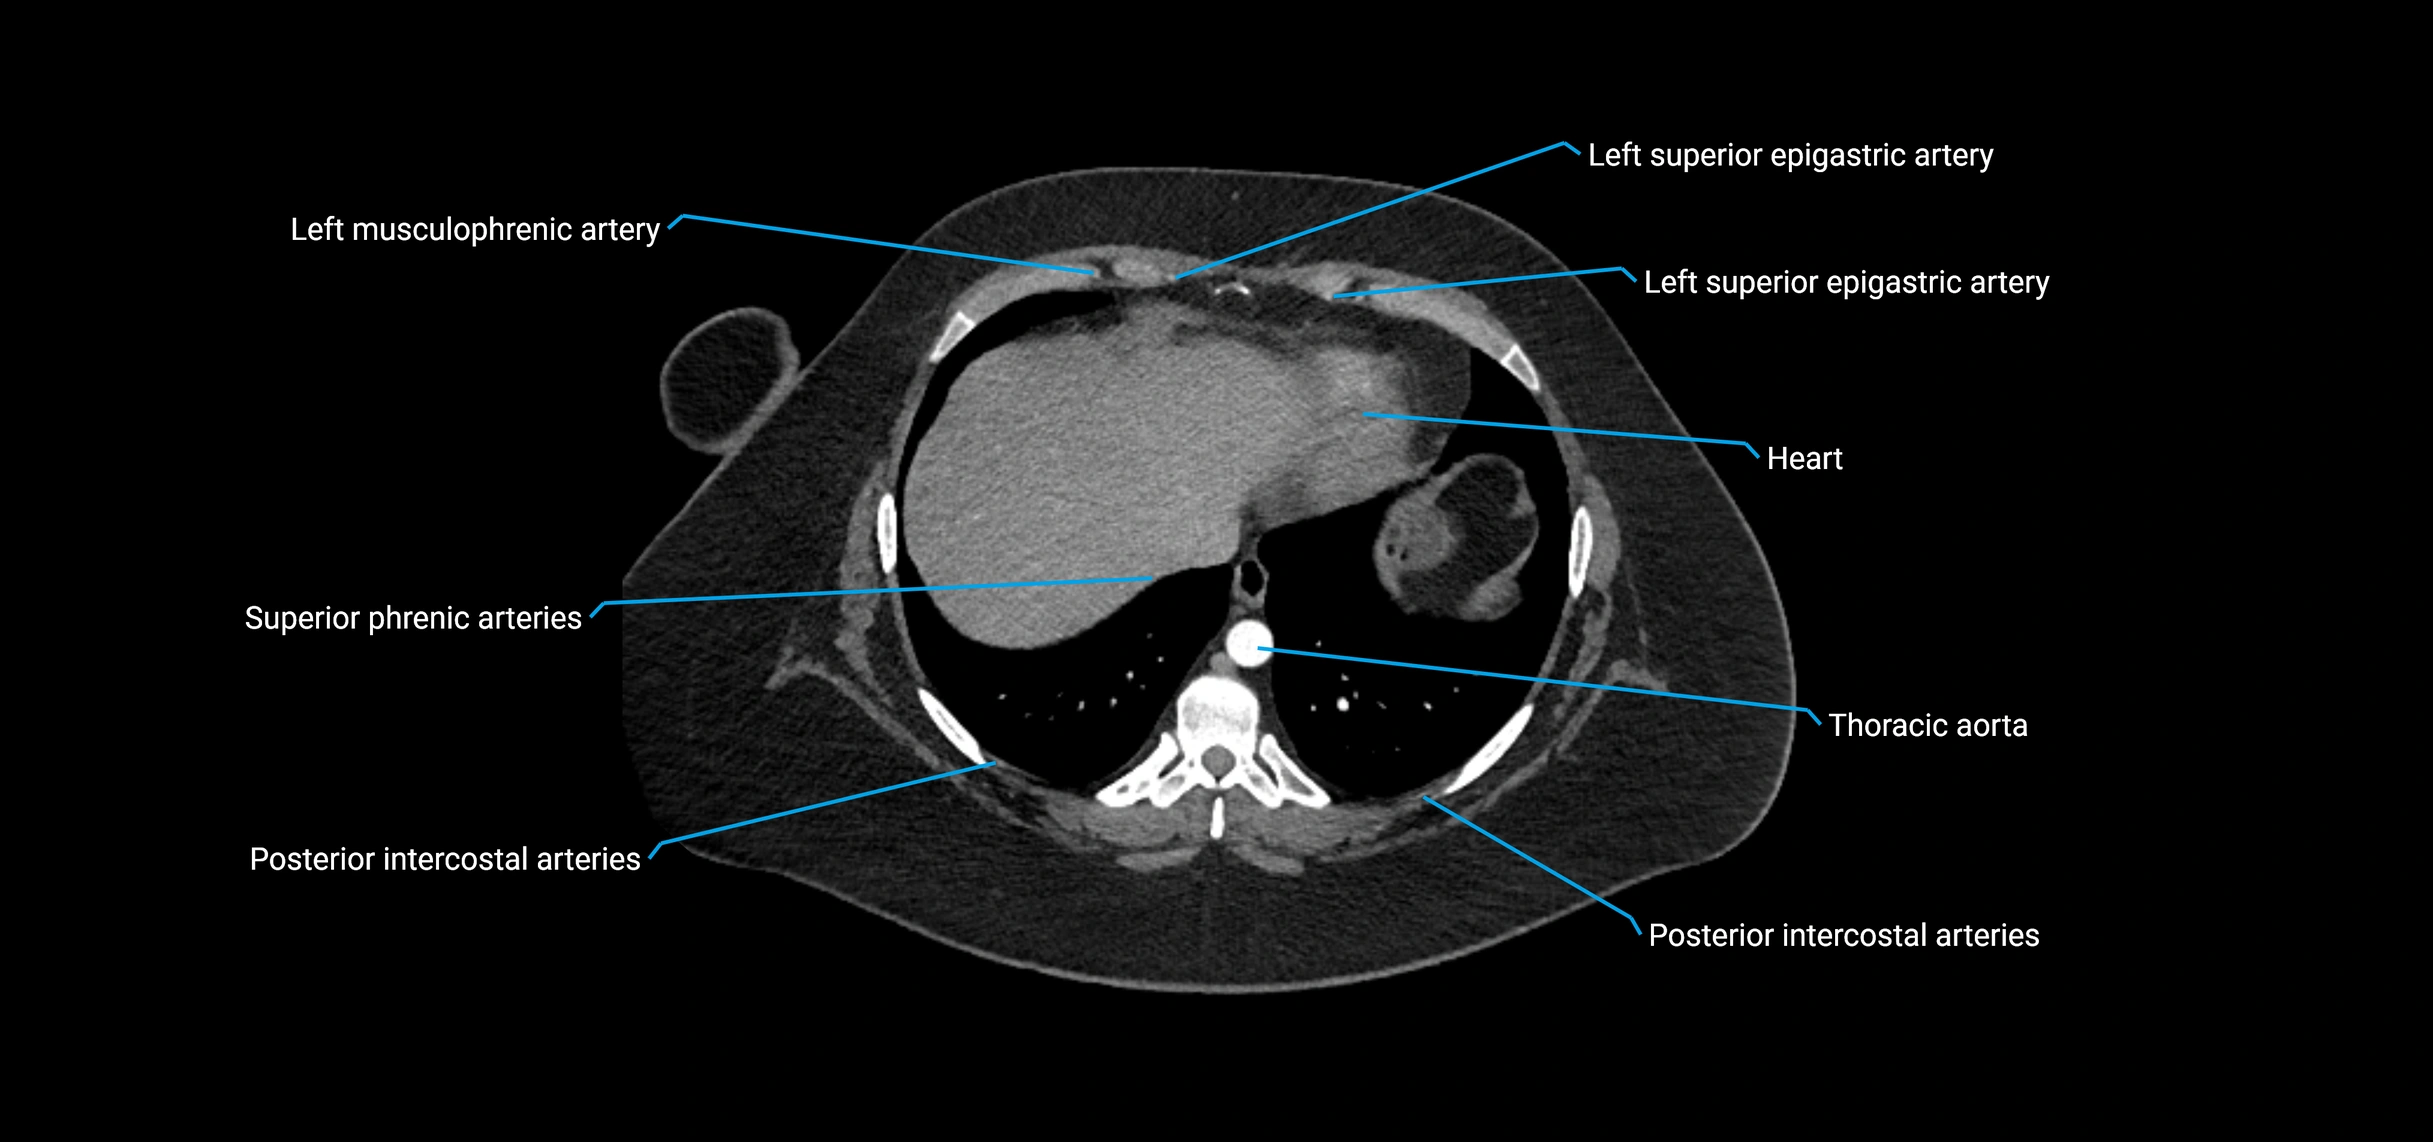

MRI images

image